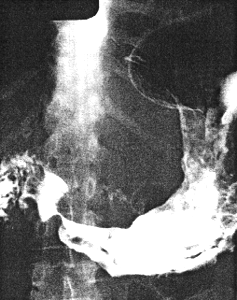

Case 33.8 J.P., 39 year old male. Radiology: 5.0cm long constricting pyloric filling defect. Smooth, concave indentation base of duodenal bulb (Fig. 33.8). Operation: Entire lesser curvature of stomach, part of greater curvature and pyloric region infiltrated. Serosal spread, lymph node and probable liver metastases. Duodenum appears normal. Billroth II. Gastric histology: well differentiated adenocarcinoma with widespread infiltration of gastric submucosa and mucosa. Duodenal histology: spread into submucosa and to lesser extent into mucosa of proximal 2.0 cm of duodenum.

![]() | |

| Fig. 33.8 A-D. Case J.P. Constricting pyloric filling defect. Smooth, concave indentation base of duodenal bulb. | |